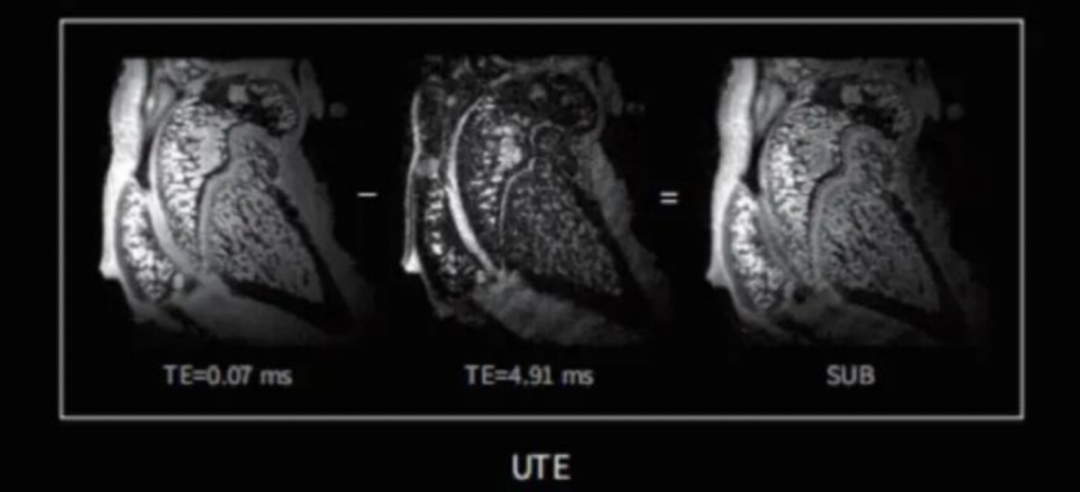

小动物骨形态研究

核磁共振作为检验尾椎间盘蜕变的金标准,在骨骼、关节区域的成像具有更高的清晰度以及空间分辨率。例如椎间盘病变大鼠使用T2WI成像,可以观察髓核的病变及病灶区域骨髓的流失情况(如图6)。膝关节核磁共振减影成像可以突出感兴趣的结构或病变区(如图7),在膝关节疾病的诊断和研究中发挥重要作用。

图6 大鼠椎间盘T2WI成像

图7 小鼠膝关节UTE成像